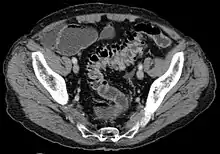

CT scan showing extensive diverticulosis of the sigmoid colon

Diverticular disease

Diverticulosis is defined by the presence of multiple pouches (diverticula) in the colon.[22] In people without symptoms, these are usually found incidentally during other investigations.

While a good history is often sufficient to form a diagnosis of diverticulosis or diverticulitis, it is important to confirm the diagnosis and rule out other pathology (notably colorectal cancer) and complications.

• Contrast CT is the investigation of choice in acute episodes of diverticulitis and where complications exist.